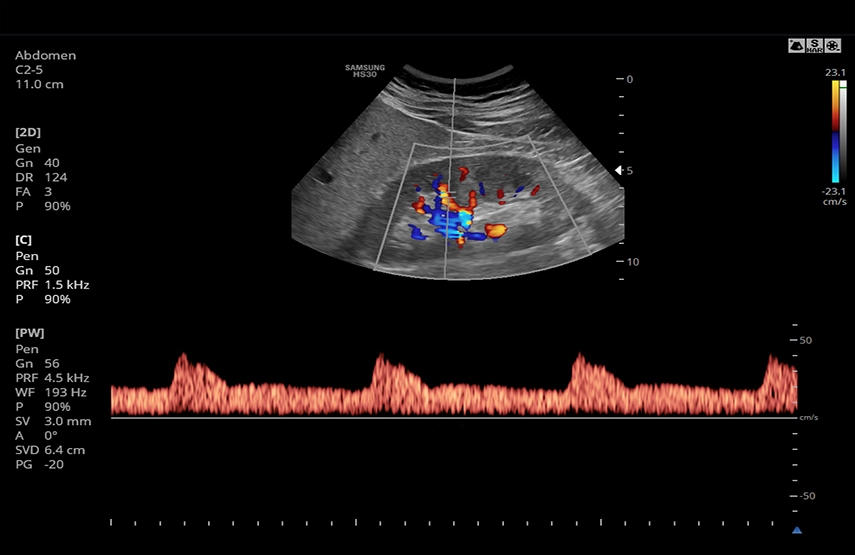

Многофункциональный ультразвуковой сканер с оптимальным набором функций и режимов сканирования для всех видов исследований, включая цветной, энергетический, направленный энергетический, тканевой, импульсный и непрерывноволновой допплер.

УЗИ сканер Samsung Medison HS30 – удобный аппарат, приспособленный под нужды врачей. В строении сканера предусмотрены держатели для кабелей датчиков, нагреватель геля, боковой карман, чтобы необходимые вещи всегда были под рукой. Помимо стандартных режимов сканирования поддерживает современные функции, позволяющие расширить возможности диагностики и повысить ее точность, Elastoscan, Strain+, NeedleMate и др. Система имеет оптимальное соотношение цена/качество/функционал в своем сегменте и станет прекрасным выбором для частного кабинета или небольшой клиники общего профиля. Абдоминальные исследования, акушерство, гинекология, кардиология, ангиология, нефрология, урология, онкология, педиатрия, неонатология, исследования костно-мышечной системы, поверхностных органов, молочной железы, ТКД.

- CD - цветное допплеровское картирование с возможностью изменения допплеровского угла.

- PW - импульсно-волновой допплер, steering - изменение допплеровского угла в режимах CD и PD, автоматический анализ допплеровских кривых.

- Конвексный датчик C2-5, 2-5 МГц, угол обзора 75 градусов;

Почки в цвете в S-Harmonic